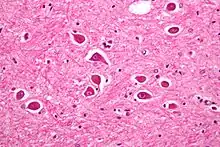

| Micrograph of Alzheimer type II astrocytes, as may be seen in hepatic encephalopathy | |

There are various explanations why liver dysfunction or portosystemic shunting might lead to encephalopathy. In healthy subjects, nitrogen-containing compounds from the intestine, generated by gut bacteria from food, are transported by the portal vein to the liver, where 80–90% are metabolised through the urea cycle and/or excreted immediately. This process is impaired in all subtypes of hepatic encephalopathy, either because the hepatocytes (liver cells) are incapable of metabolising the waste products or because portal venous blood bypasses the liver through collateral circulation or a medically constructed shunt. Nitrogenous waste products accumulate in the systemic circulation (hence the older term "portosystemic encephalopathy"). The most important waste product is ammonia (NH3). This small molecule crosses the blood–brain barrier and is absorbed and metabolised by the astrocytes, a population of cells in the brain that constitutes 30% of the cerebral cortex. Astrocytes use ammonia when synthesising glutamine from glutamate. The increased levels of glutamine lead to an increase in osmotic pressure in the astrocytes, which become swollen. There is increased activity of the inhibitory γ-aminobutyric acid (GABA) system and the energy supply to other brain cells is decreased. This can be thought of as an example of brain edema of the "cytotoxic" type.[13]